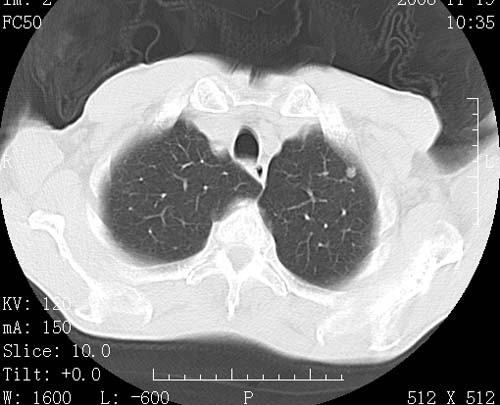

术前查体,双肺部结节是转移?结核?请点评

1)符合食管癌表现。2)两肺及纵隔淋巴结多发性转移瘤。3)左肺上叶舌段及两肺下叶炎症感染。

1)符合食管癌表现。2)两肺及纵隔淋巴结多发性转移瘤。3)左肺上叶舌段支气管扩张伴感染.

食管癌伴双肺转移,评述:肺部毛细血管网丰富,全身血液均快速流经肺部,癌细胞容易过滤定植,形成转移瘤,影象特点为以毛细血管末梢为中心的结节灶,边缘光滑锐利,少见有中心空洞着,不同来源的转移瘤可有各自特点,如甲状腺癌为双肺弥漫性微结节,本例有原发灶,双肺影象灶典型,左肺舌段条带状网格样伴胸膜天幕征,可视为癌性淋巴管炎。

符合食管癌表现。两肺及纵隔淋巴结多发性转移瘤。双肺还有支扩表现.

支持胃镜食管癌诊断。两肺及纵隔淋巴结多发性转移瘤。左肺上叶舌段及两肺下叶炎症感染。

1)符合食管癌表现。2)两肺及纵隔淋巴结多发性转移瘤。3)左肺上叶舌段支气管扩张伴感染

左肺舌段有斑点钙化灶,能否说明是结核而不是转移?如果是转移将放弃手术改成化疗,如果是结核将考虑择期手术